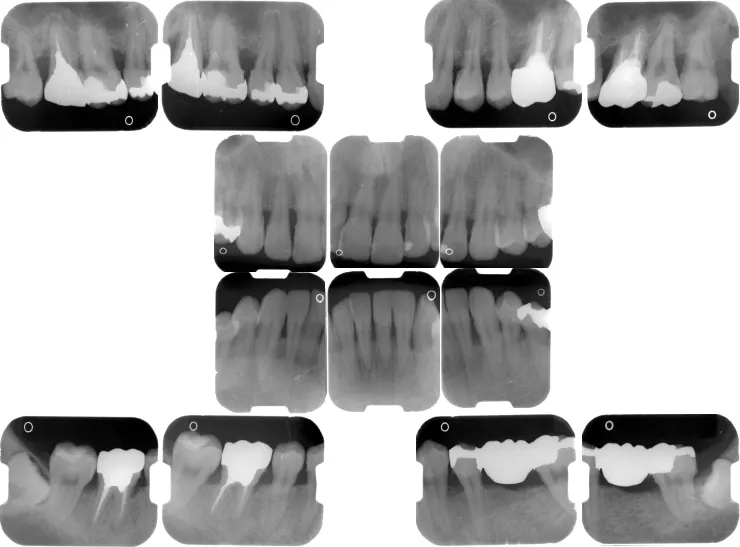

症例:一見カリエスフリー(ムシ歯のない)症例の

ご説明:説明は口腔写真とレントゲンを対比して、2つのモニタで表示した画面を見ながら行います。 また、口腔写真やレントゲン写真は 、画像を印刷してファイリングしてからお渡しするサービスを行っています。

| 内 訳 | ・初診料 ・歯周基本検査 ・歯周疾患指導管理 ・衛生実地指導 ・口腔写真 ・レントゲン全顎撮影 |